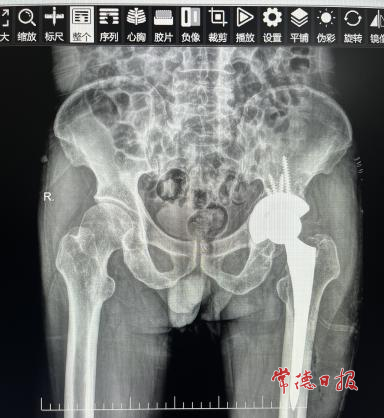

经检查,唐大爷被确诊为“全髋关节置换术后髋臼假体松动”。影像资料显示,其髋臼假体周围出现了大量骨缺损,这意味着初次置换的关节已无法继续使用,必须进行二次“重启置换”。

在麻醉科的紧密配合下,手术团队凭借精湛的技术,小心翼翼地将已松动的旧假体取出,精准清理关节腔后,采用合适的植骨材料对缺损部位进行修复,并成功为唐大爷植入了新型适配的髋臼假体。整个手术历时仅2小时,过程精准、出血量少。术后第二天,唐大爷便能开始在床上进行功能锻炼;术后第三天,他已能借助助行器下地行走。